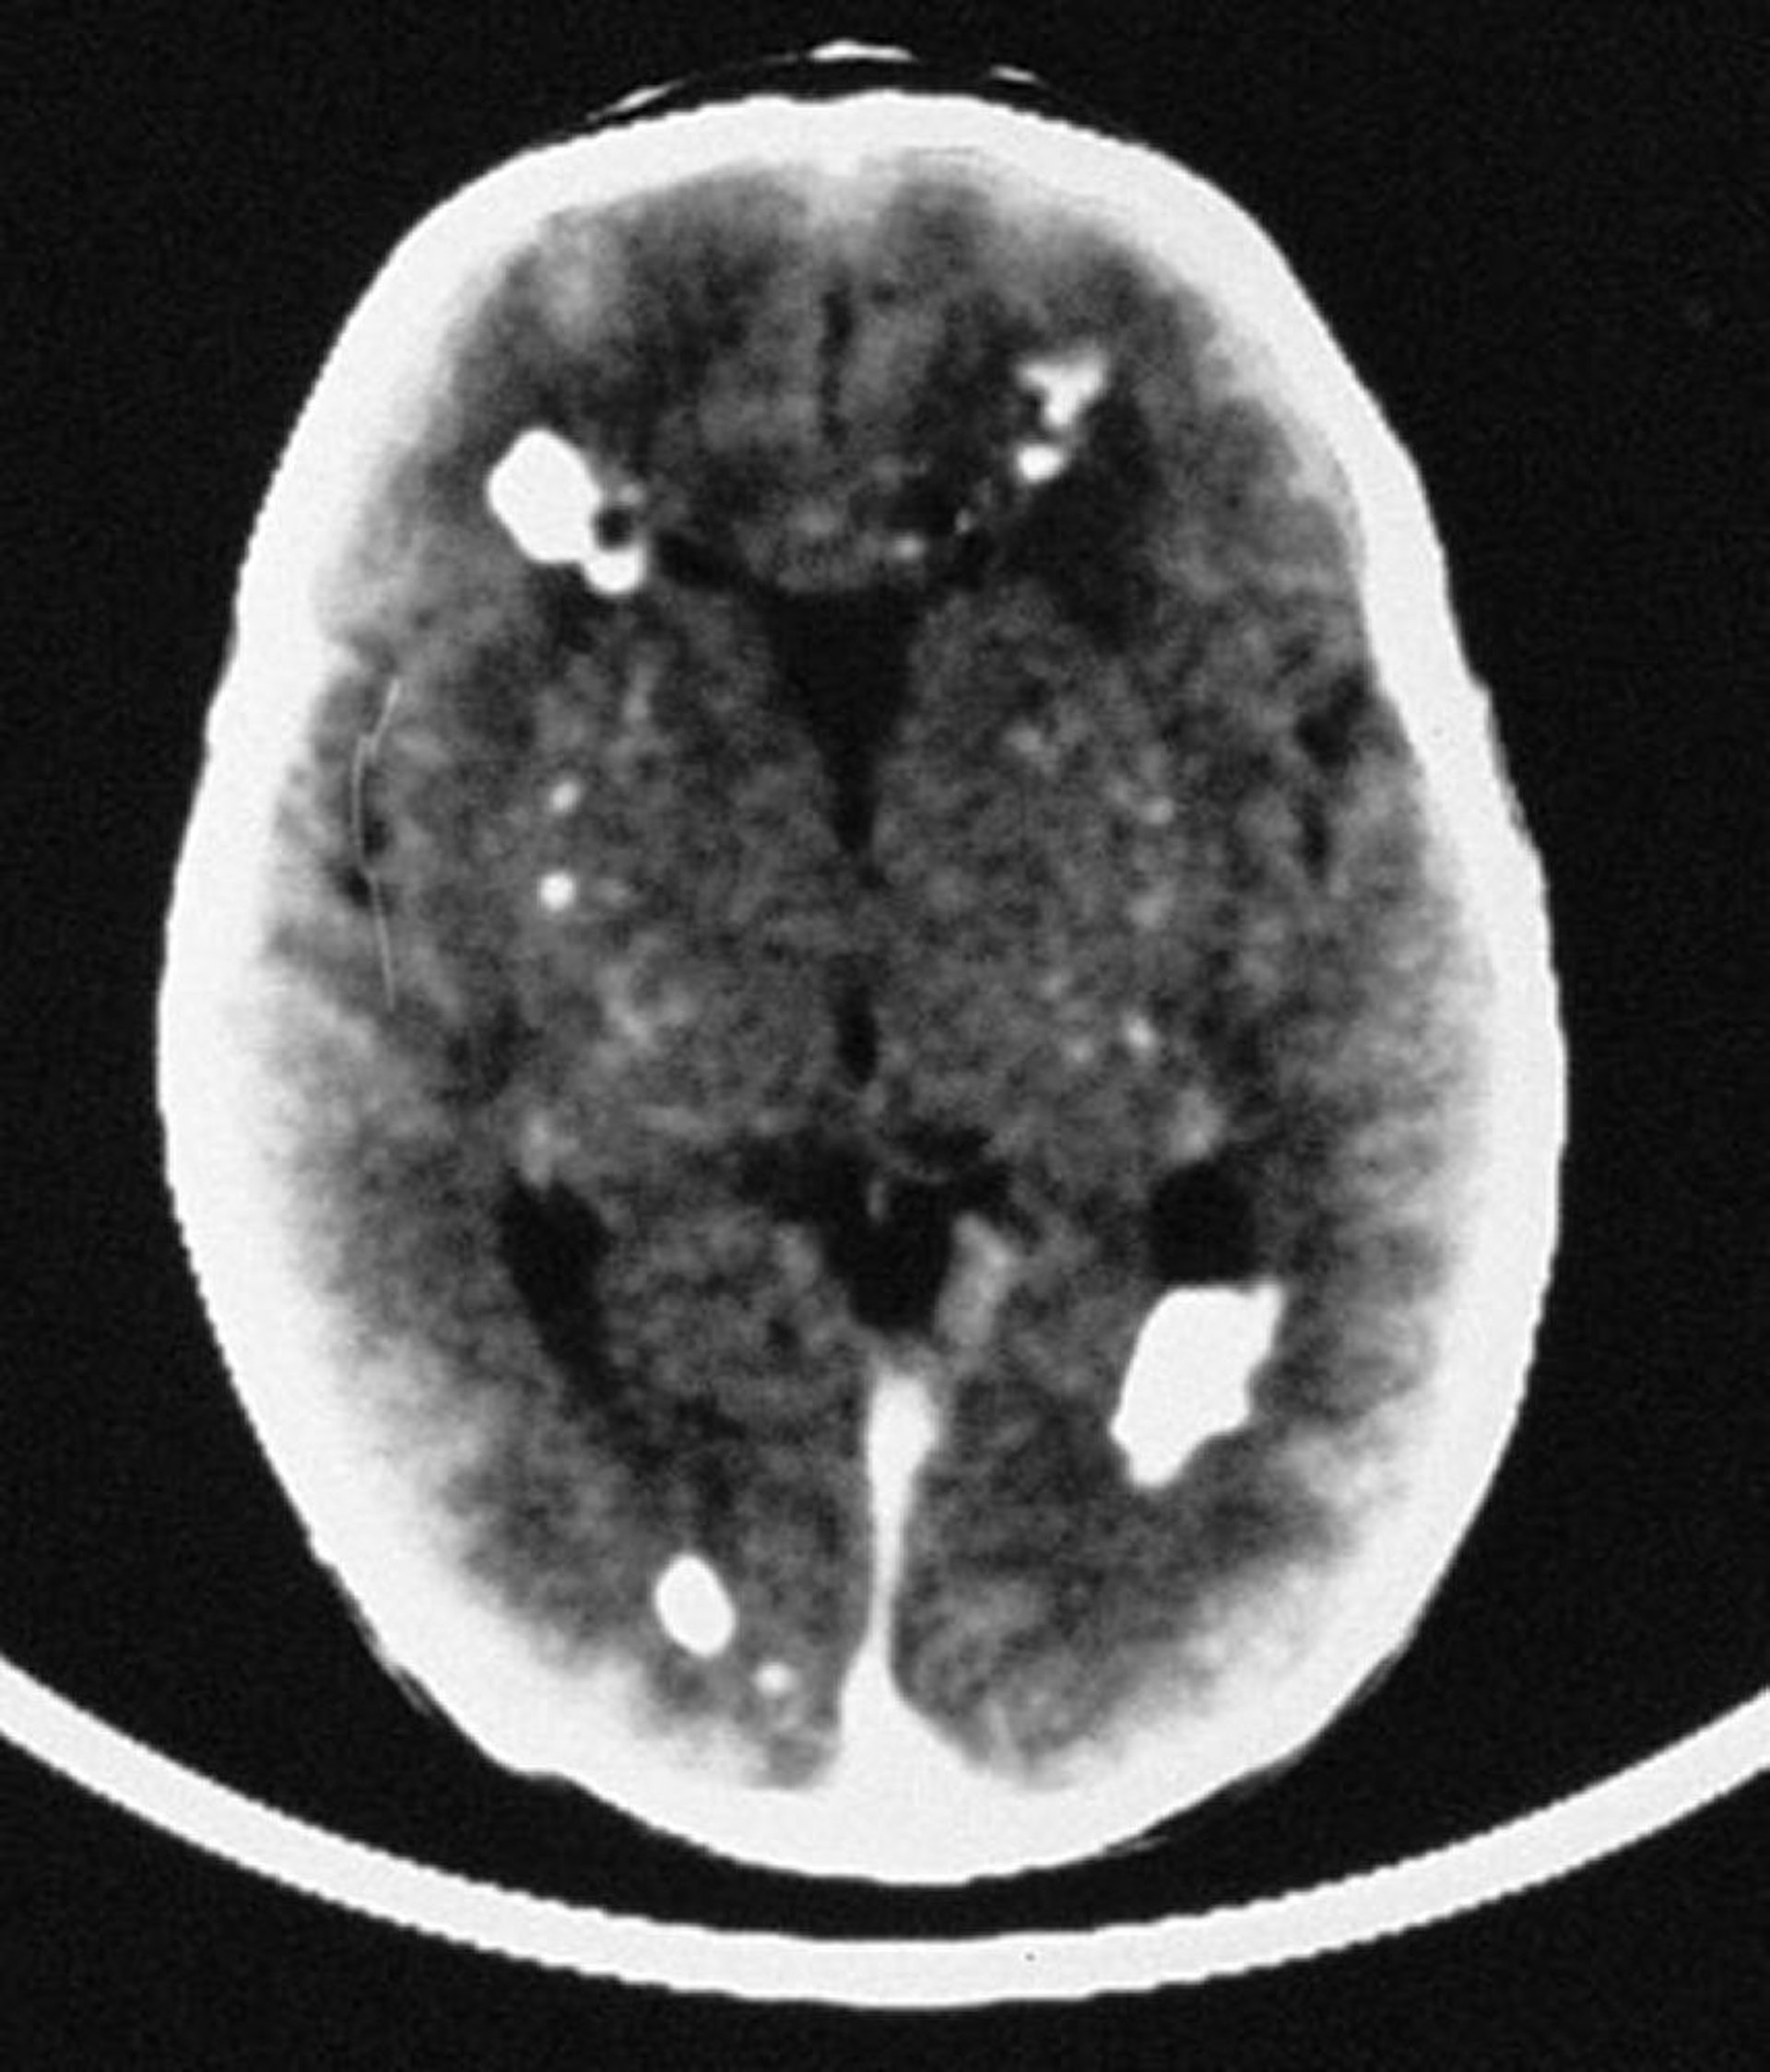

Kongenitale Zytomegalievirusinfektion

In diesem Bild zeigt das CT multiple intrakranielle Verkalkungen, die meist periventrikulär verteilt sind, aber auch vaskuläre Strukturen des Gehirns betreffen.

By permission of the publisher. From Demmler G: Congenital and perinatal infections. In Atlas of Infectious Diseases: Pediatric Infectious Diseases. Edited by CM Wilfert. Philadelphia, Current Medicine, 1998.